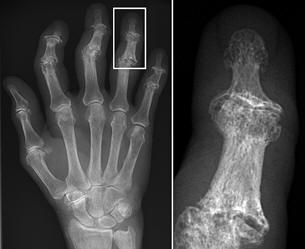

Normal hand RA - Damaged finger joints RA - Fused finger joint

Normal hand bones RA - Damaged hand bones RA - Damaged hand

Description English:

X-ray of right fourth proximal

interphalangeal (PIP) joint with bone erosions by rheumatoid arthritis. Taken October 2002. Same joint is partially healed on a follow-up X-ray

after treatment with conventional disease-modifying

antirheumatic drugs(DMARDs) one year later: File:X-ray of right fourth PIP joint with partially healed bone erosions by

rheumatoid arthritis.jpg